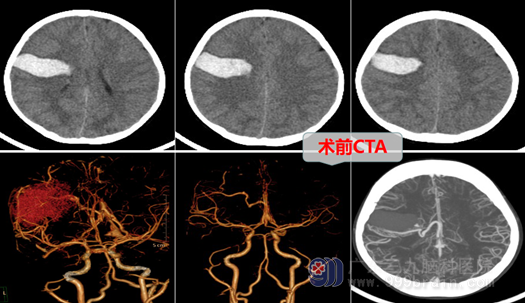

住入神经外十科后,很快做了CTA检查,结果显示:右侧额叶脑出血并破入蛛网膜下腔,基底节区动静脉畸形(AVM),脑血管DSA显示:基底节区AVM伴发动脉瘤,由豆纹动脉供血,静脉回流至脑深部直窦,病变不适合做栓塞治疗,只能开颅手术,但手术也确实是有比较大的风险。完善术前检查后,欧阳辉带领团队认真讨论,制定了周密的手术方案,决定在全麻下行右侧豆纹动脉远端动脉瘤夹闭术+右侧额叶动静脉畸形切除术及血肿清除术。术中他们如履薄冰、如临深渊,小心翼翼,在显微镜放大下,顺利夹闭了动脉瘤,切除了畸形血管,清除了血肿,现在小女孩已顺利进入康复期。